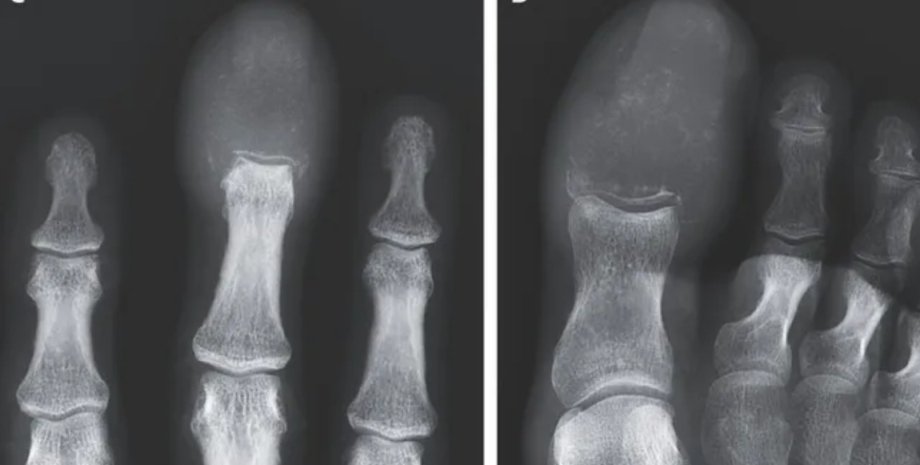

Під час обстеження пацієнта лікарі виявили, що кінчики опухлих пальців були на дотик щільними і почервонілими. Подальше сканування показало, що ракова пухлина повністю замінила кістки в пальцях руки та ноги чоловіка. Йдеться про літичні ураження — області, де руйнується кістка, залишаючи отвори або порожні простори в скелеті. Такі ураження зазвичай спричинені патологічним процесом, наприклад, раком.

Давно відомо, що рак, який поширився на кістки, може імітувати подагру або остеомієліт. Але рентгенографія допомагає поставити точний діагноз.

На основі рентгенограми у 55-річного пацієнта було діагностовано акрометастаз, який є рідкісною формою раку, що зустрічається нижче ліктя або коліна. Акрометастази становлять лише близько 0,1% випадків поширення раку на кістки.